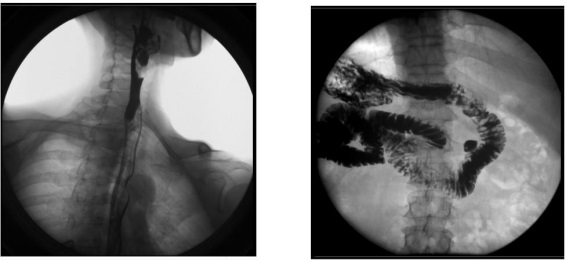

2、数字化胃肠功能:适用于胃肠道造影检查,如食管造影、上消化道造影、全消化道造影等。

1) 消化内科:可检查直肠炎、结肠炎等;

临床表现为腹痛、便秘等,症状为便血、黑便等。

2) 肛肠科:可应用气钡双重造影和排便造影(DFG)功能,可检查大肠的细小病变,如小息肉、早期肿瘤、溃疡等效果良好;可检查肛管炎、耻骨直肠肌综合症、骶骨部畸胎瘤、直肠前突、直肠内套叠、肛门直肠损伤和异物等检查。

3、其他造影:适用于各种普通及特殊造影,如口服胆囊造影、静脉胆道造影、T 管造影、逆行胰胆管造影(ERCP)、静脉肾盂造影(IVP)、子宫输卵管造影等。

1) 妇科:可检查输卵管堵塞、输卵管粘连、输卵管积水等慢性输卵管疾病导致的不孕,可明确显示输卵管堵塞的部位、程度及性质,还可辨认子宫内膜情况,输卵管和盆腔的结核病变情况;

2) 肝胆外科:胆管手术后,切开胆总管植入 T 管引流,起支撑作用,防止术后胆总管狭窄,术后应用胃肠机进行胆管造影(T 管造影),检查胆道内有无残留结石及异物,是否通畅无阻, 对手术进行评估;